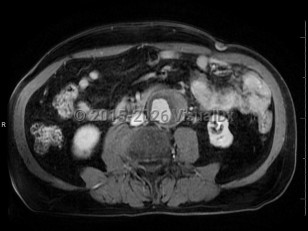

Polycystic kidney diseasePolycystic kidney disease

Abdominal aortic aneurysmAbdominal aortic aneurysm